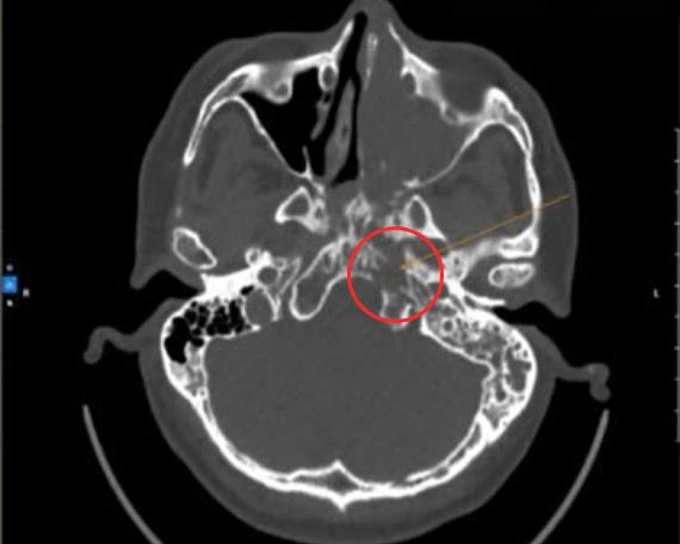

Kết quả nội soi tại Phòng khám Đa khoa Tâm Anh Quận 7 cho thấy khối u lấp đầy hốc mũi trái, che kín cửa mũi sau và vùng hòm kèm chảy máu. Ảnh CT ghi nhận tổn thương lan vào lấp đầy xoang sàng, xoang trán, xoang bướm trái, vòm mũi họng hai bên.

ThS.BS.CKI Trương Tấn Phát, Trưởng Đơn vị Tai Mũi Họng, cho biết ông Lăng bị viêm mũi xoang xuất tiết, chỉ định sinh thiết u hốc mũi do nghi ngờ ác tính. Kết quả sinh thiết là ung thư hốc mũi, dạng biểu mô tế bào vảy. Bác sĩ phẫu thuật cắt khối u ác tính và xương bị xâm lấn cho người bệnh.